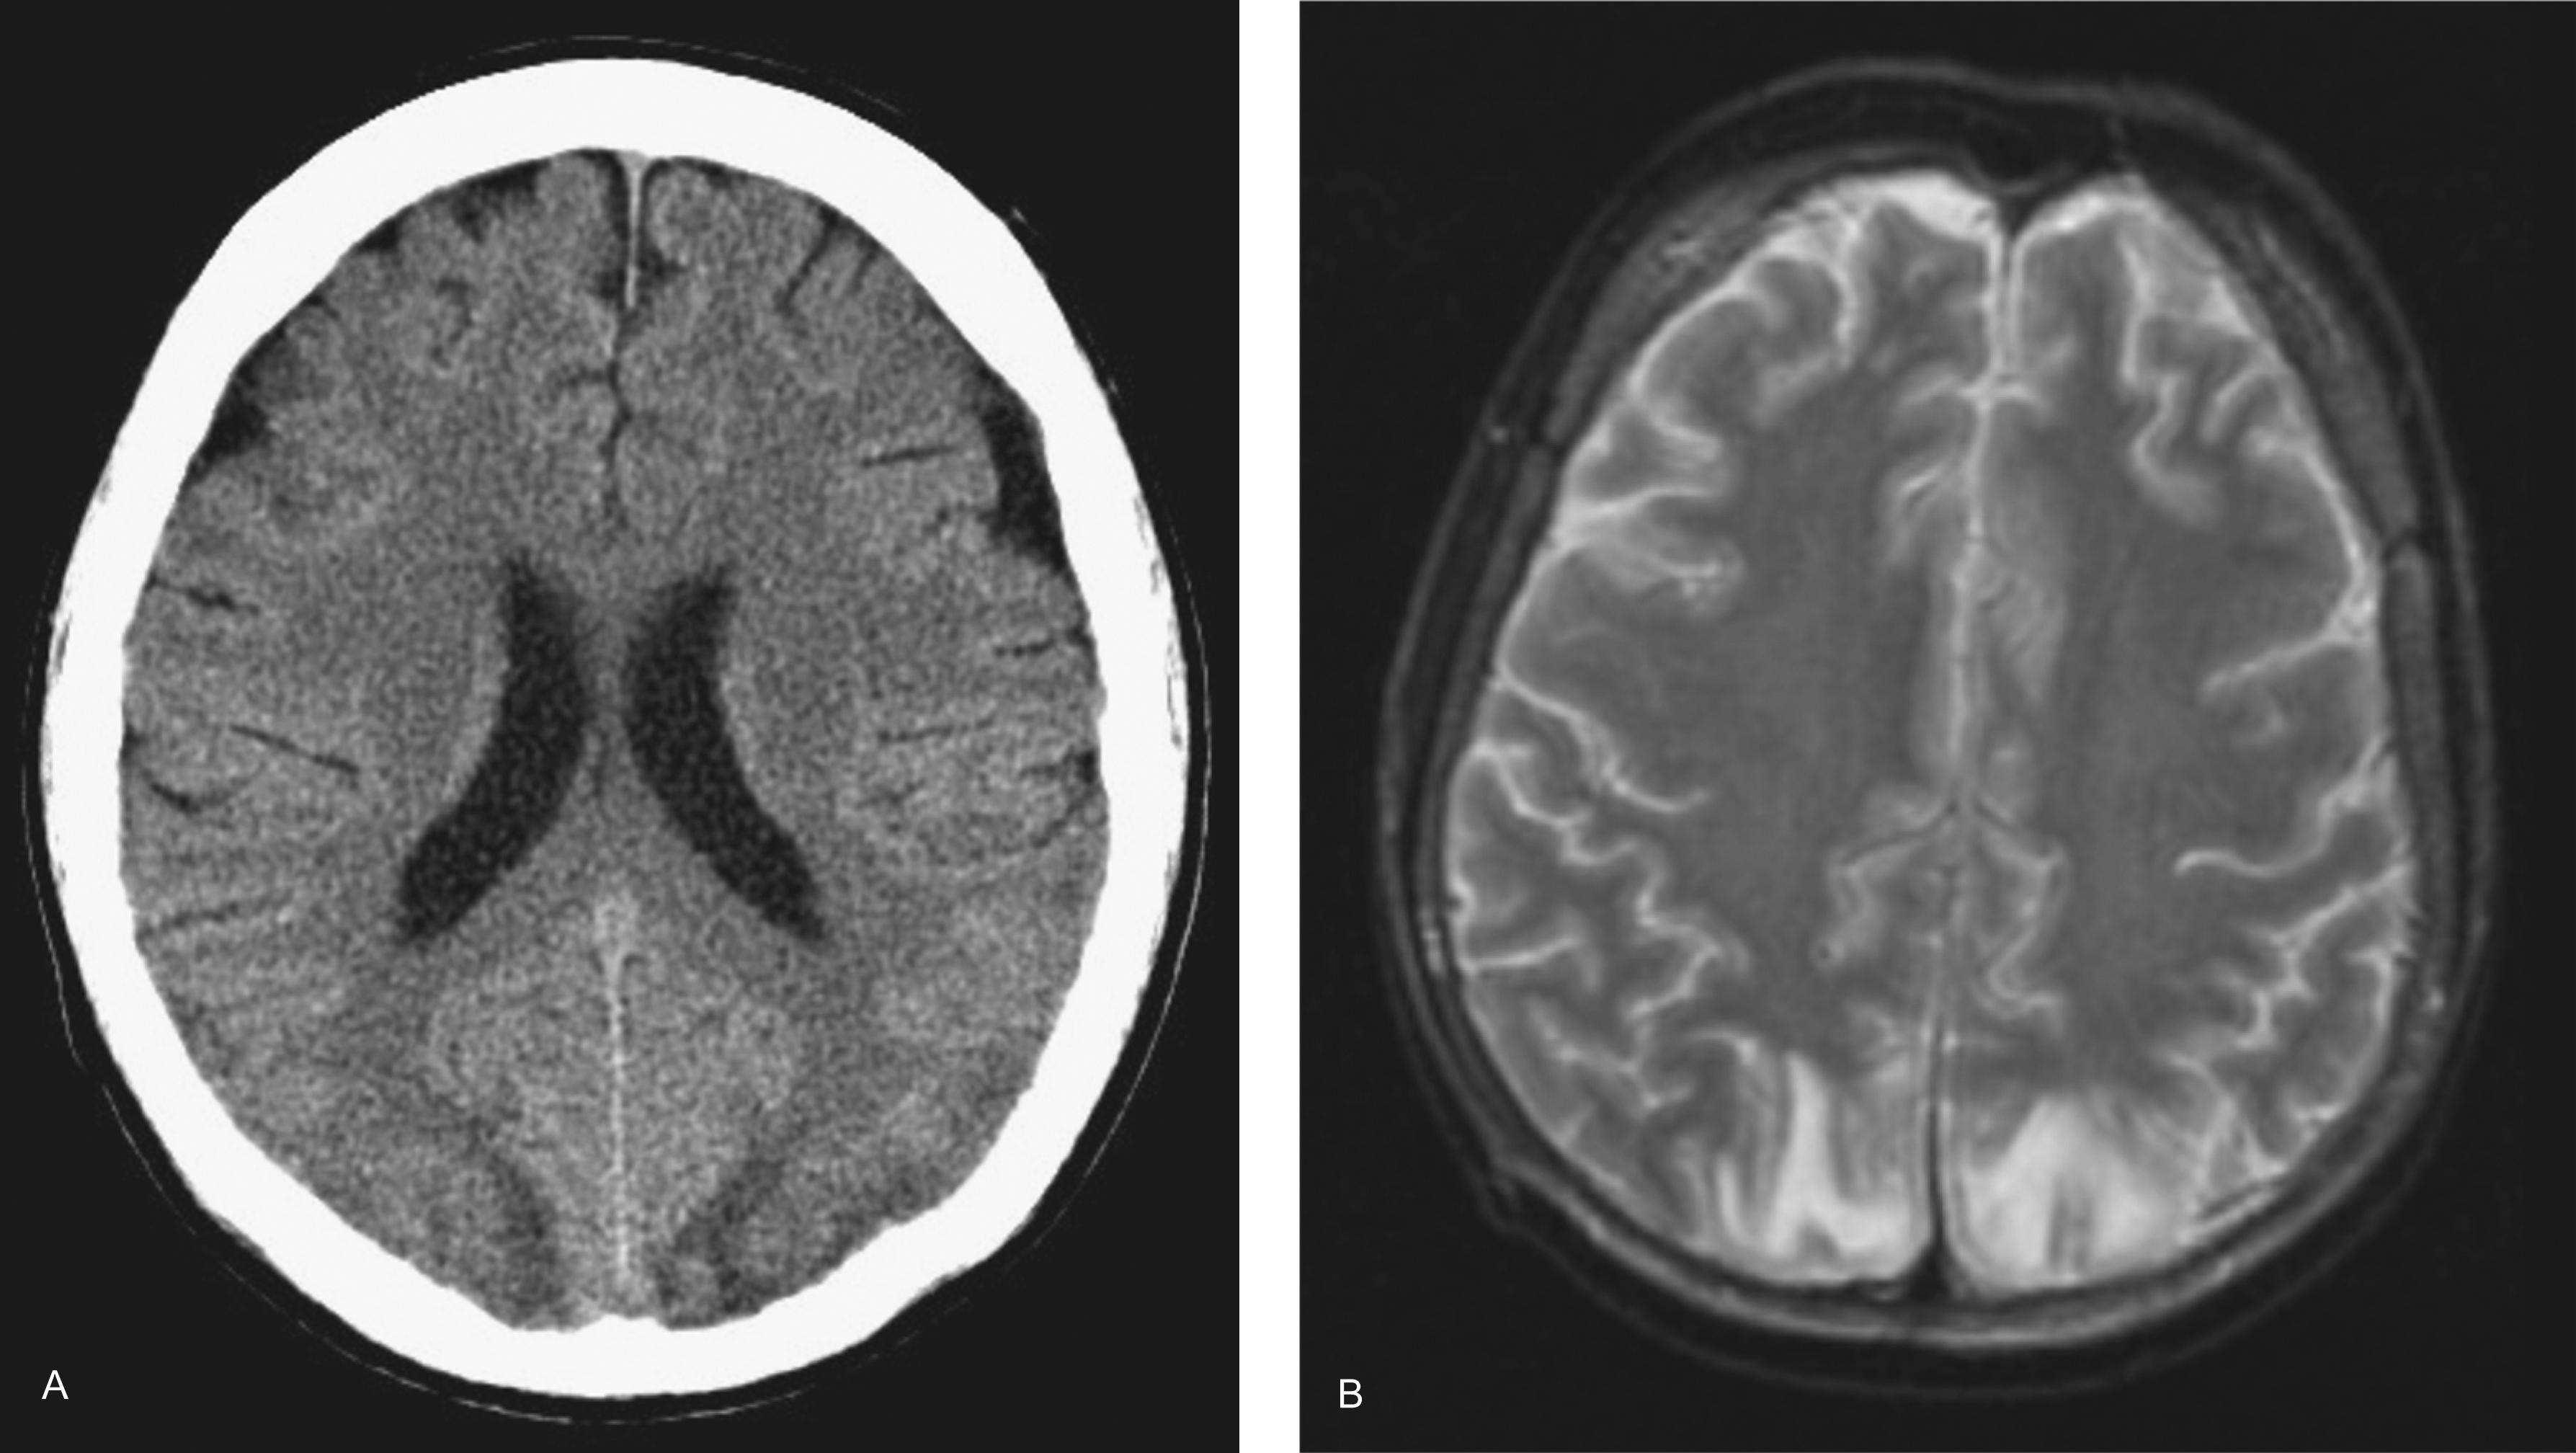

Seizures are common. They are usually generalized convulsions, may be multiple, and are often multifactorial in etiology. In acute renal failure, convulsions commonly occur several days after onset, during the anuric or oliguric phase. In chronic renal failure, they tend to occur with advanced disease, often developing preterminally; they may relate to the uremia itself or to electrolyte disturbances, medications (such as penicillin, aminophylline, or isoniazid), or an associated posterior reversible encephalopathy syndrome (characterized by vasogenic white-matter edema predominantly localized to the posterior cerebral hemispheres on imaging studies, as shown in Fig. 16-1 ). Their incidence has declined, perhaps because of more effective treatment of renal failure and its complications. Seizures also occur in patients undergoing hemodialysis as part of the dialysis dysequilibrium syndrome (discussed later). Focal seizures sometimes occur. Occasionally patients develop nonconvulsive status epilepticus that may not be recognized unless an EEG is obtained.

Figure 16-1, Imaging findings of a patient with seizures who was diagnosed with posterior reversible encephalopathy syndrome. A , Axial computed tomography (CT) scan demonstrates bilateral low-density involvement of the occipital lobes. B , Axial T2-weighted magnetic resonance imaging (MRI) shows high signal intensity lesions without mass effect involving white matter bilaterally in the occipital lobes.